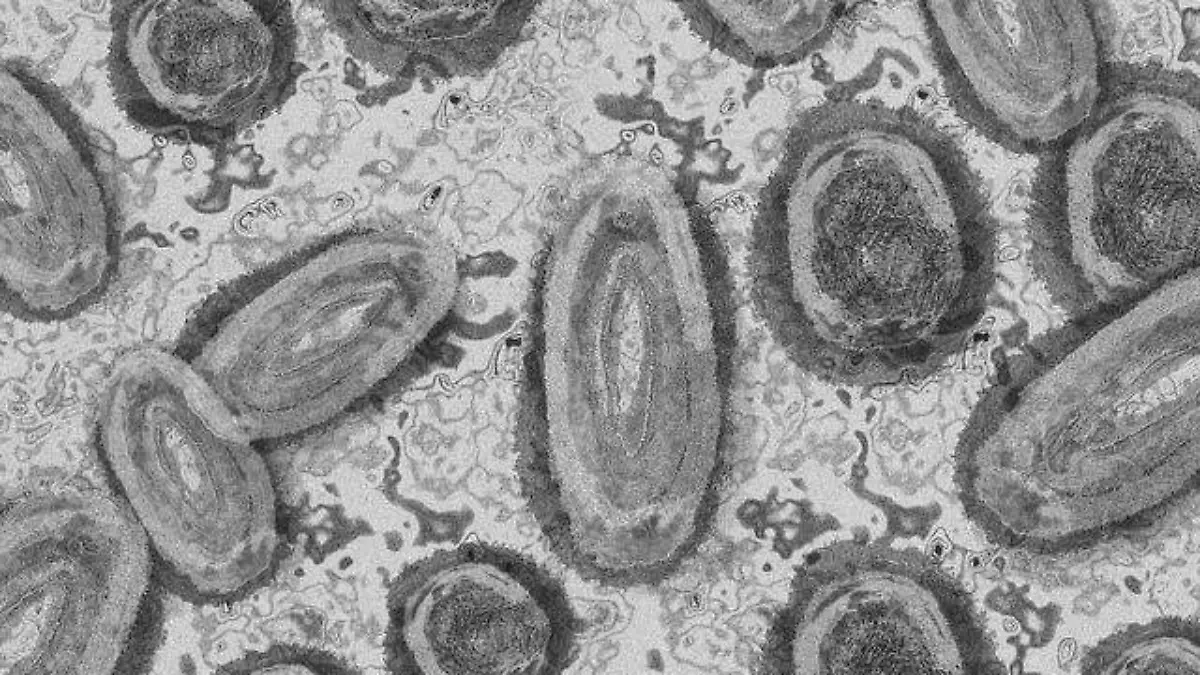

A pesar de que en Guerrero no se ha presentado casos de la viruela símica o del mono, la Secretaría de Salud en el estado informó que se reforzó la vigilancia epidemiológica ante el anuncio de la Organización Mundial de la Salud.

La Secretaría de Salud, Aidé Ibarez Castro dijo que las medidas sanitarias son las mismas que las del Covid -19 para reducir el riesgo de contraer el virus del mono.

Comentó que existe antecedente de casos de contagio por exposición física directa, contacto con piel lesiones o contacto sexual. Así como como con ropa o utensilios de uso personal, además de haber viajado a un país con presencia de casos.

En México a esta fecha en el país se han confirmado 60 casos de viruela símica, de las cuales el InDRE ha confirmado 59 en once entidades federativas: Quintana Roo con uno, Nuevo León 2, Sinaloa 1, Ciudad de México 35, Veracruz 2, Colima 1.

Así también en Jalisco se tiene 12 casos y el Estado de México 2, Oaxaca 1, Tabasco 1 y Baja California 1.